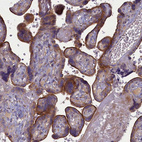

Immunohistochemical staining of human placenta shows strong membraneous positivity in trophoblastic cells.